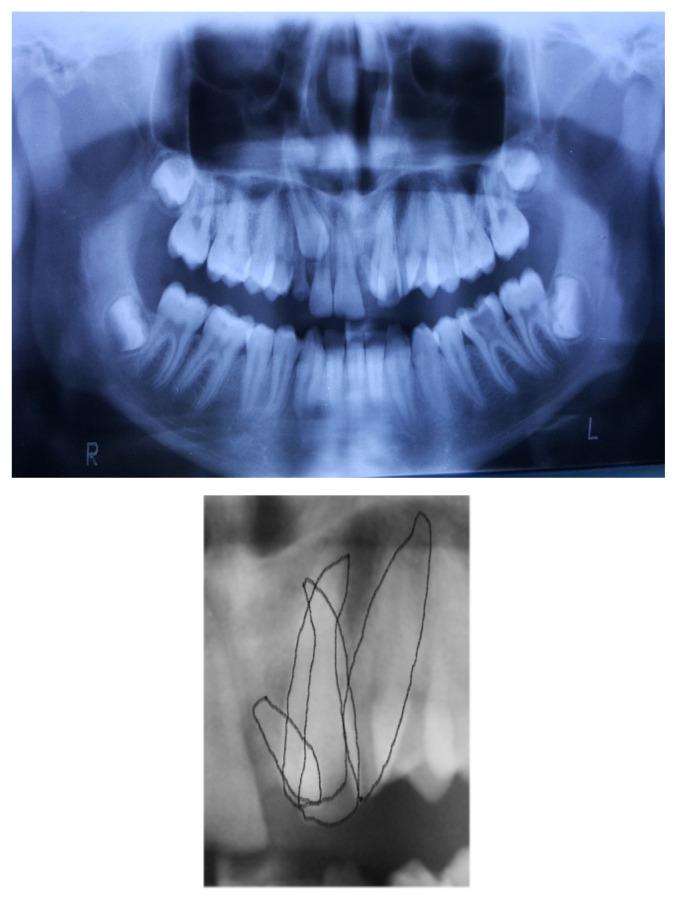

Tooth number abnormalities may occur under the influence of genetic or environmental factors which intervene in the tooth formation stages (induction and proliferation), most commonly the permanent dentition being affected. The result is the appearance of dental anomalies with numerical deficiency (hypodontia, anodontia), or with dental excess (hyperodontia, over-teeth). In this paper we report a case of a 15-year-old boy with associated abnormalities of permanent dentition: mesiodens and palatal impacted cuspid at the maxillary dental arch and incisor anodontia at the mandibular dental arch. Orthodontic treatment aimed at resolving maxillary dental crowding, obtaining dental alignment, a stable and functional occlusal relationship and a satisfactory smile for the patient.

牙齿数目异常可能在影响牙齿形成阶段(诱导和增殖)的遗传或环境因素作用下发生,最常受影响的是恒牙列。结果是出现牙齿数目不足(缺牙症、无牙症)或牙齿过多(多生牙、额外牙)的牙齿异常情况。在本文中,我们报告了一例15岁男孩伴有恒牙列相关异常的病例:上颌牙弓有正中多生牙和腭侧埋伏尖牙,下颌牙弓有切牙无牙症。正畸治疗旨在解决上颌牙列拥挤问题,实现牙齿排列整齐、稳定且功能良好的咬合关系,并为患者打造令人满意的笑容。